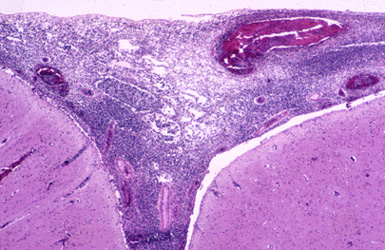

Question 24: The most likely cause of the pathology in the 59 year old patient illustrated below is:

Incorrect. The illustrated lesion is meningitis. The most likely agent in a 59 year old patient is pneumococcus.

Correct. The illustrated lesion is meningitis. The most likely agent in a 59 year old patient is pneumococcus.